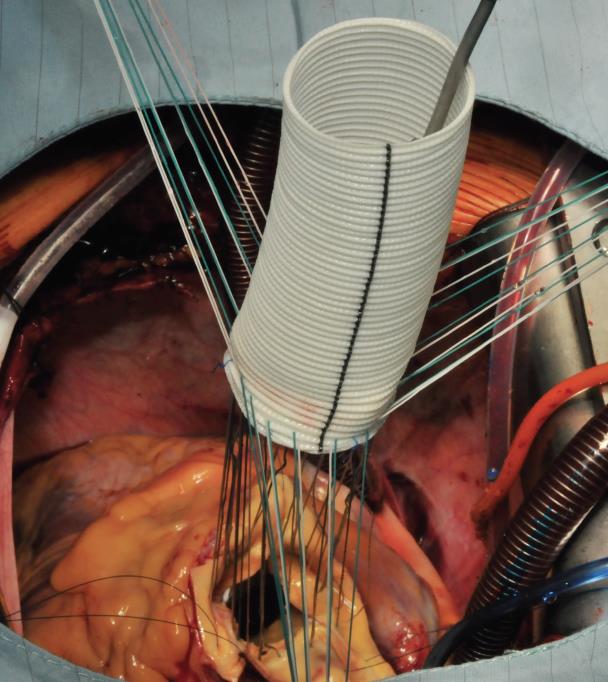

The procedure starts with the proximal suture of the composite graft prosthesis to the aortic annulus using separated mattress suture of 2.0 Ethibond backed with small Teflon pledgets. The first suture is placed at the level of the commissure between the left and right coronary sinuses and the following are stitched in a clockwise fashion (Image 1). The sutures are placed through the annulus with the pledgets left either on the aortic side thus everting the annulus, but in small annular diameters. The author prefers to stich these sutures from the ventricular side to the aorta, therefore the pledgets lie under the aortic annulus. Then the sutures are placed through the sewing ring of the composite graft prosthesis (Image 2) which is later on parachuted down to the aortic annulus (Image 3). The sutures are then tightened and the valve is placed into the outflow tract of the left ventricle (this provides excellent hemostasis).

Image 3: The composite graft is then parachuted into the aortic annulus (mechanical valve) or placed in a supra-annular position when a bioprosthetic valve has been used. The sutures are tightened and cut. At this time, the core temperature has usually be brought to 28 or 30°C to proceed with the distal anastomosis at the level of the proximal (open) aortic arch.